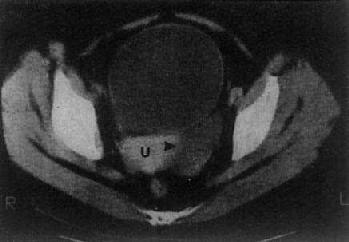

(三)卵巢囊肿或肿瘤 单纯的卵巢囊肿,大多是潴留囊肿,常较小,CT易于显示。表现为囊性低密度影,CT值接近水,边界光滑整齐,大小常为数厘米(图4-5-8)。囊性畸瘤表现为密度不均的低密度肿块,内含多种组织如脂肪、钙化、牙或骨组织。皮样囊肿,其壁常有钙化。卵巢囊腺瘤常较大。浆液性囊腺瘤可为单房性或多房性,壁较薄,少数可为双侧性。粘液性囊腺瘤壁较厚,常为多房性。它们的CT值约为15Hu,增强扫描其壁和囊均不增强。卵巢恶性肿瘤表现为盆腔或下腹部肿块,呈软组织密度,CT值40~50Hu,肿瘤大多同时具有实性和囊性部分,边缘不规则,这些有别于良性囊腺瘤和单纯性囊肿,增强扫描实体部分有增强。卵巢癌可产生腹水,其CT值偏高,可达60Hu,30%的病例可见腹膜或大网膜转移,表现为前腹壁后方扁平形软组织肿块,密度不均,境界不清。有时可见腹膜、腹腔内及肠壁间结节肿块。CT检查了解卵巢癌的范围和转移情况比判断原发癌更为重要。

图4-5-8 卵巢囊肿

子宫(U)左侧有一长圆形低密度区(→),边界清楚,其CT值与膀胱CT值相似